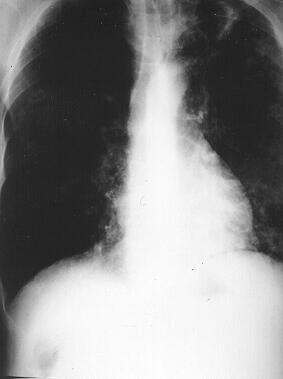

A common site of infection is the lung, known as pulmonary tuberculosis. Infection in the bronchial tubes commonly leads to a persistent cough that may produce sputum and even bloody sputum. If the infection is located in the pleural membrane surrounding the lungs and lining the chest, it may lead to chest pain aggravated by breathing (pleurisy) and shortness of breath due to an accumulation of fluid around the lung. TB can involve the central nervous system and lead to meningitis. This may lead to a headache, stiff neck and high fever. Tuberculosis meningitis usually occurs with widespread disease that has spread to multiple organs. It occurs more commonly in children and in immunosupressed people, and requires emergency evaluation and treatment.